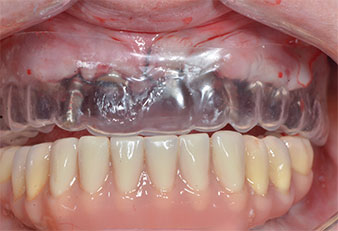

Due to the relatively hard bone (D2) in this area, the 10 mm long implant sites at positions 11 and 21 were finalized with a 4 mm diameter rotary drill, in combination with a W&H WS-75 L surgical contra-angle handpiece, the W&H Implantmed implant motor and the optional W&H Osstell ISQ module. In contrast, due to the soft bone the posterior sites were prepared to a final 3 mm diameter using the Piezomed I3P instrument. The implants were finally placed transgingivally to osseointegrate for three months (Figs. 6-10). The existing denture was retained on four provisional implants (Fig. 8).